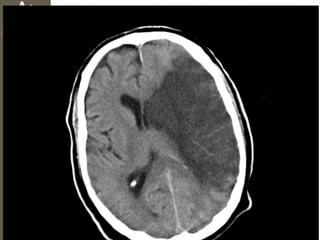

Hemorragia Subaracnoidea

• Ruptura vasos Subaracnoideos

• Fuga de Sangre hacia LCR

• > Sensibilidad por TC a 6 – 8hrs del

trauma

• Cefalea

• Fotofobia

• Anisocoria

• Signos Meníngeos

Brudzinski